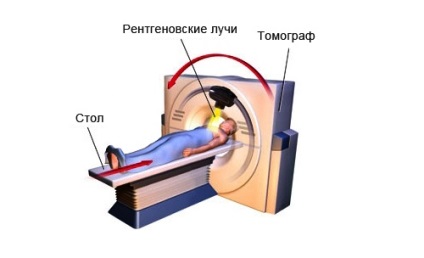

CT-vizsgálat - ez a módszer háromdimenziós megjelenítését réteges test szerkezetét. Amikor végzett CT röntgen a láb mozog, küld egymás után képeket a számítógép képernyőjén:

- Mindenesetre „cut” a láb jól látható lágy szövet és csont, felépítése és a hangerő.

- A legkisebb ciszta, tumor vagy változó kontúrok tükröződnek képek sorozatát, amely pontosan meghatározza a helyét a patológia.

- Amikor csont deformáció azonnal nyilvánvaló miatt szerkezete (a szivacsos szerkezetű vagy kortikális csont) ez történt.

Hogy a felmérés

In-beteg röntgen kamera, hogy segítsen elhelyezésére kikocsizható táblázatban.

- Foot hevederek rögzítve, úgyhogy a radiográfiai nem akaratlagos mozgások miatt, amely a kép jelenik meg homályos, elmosódott.

- A táblázat betoljuk a gép.

Elvégzésére CT lábát a beteg kerül a lapolvasó mozgatható asztal

Táblázat lehet mozgatni, a beteg segítség kell felkelni, és kijutni a röntgen kamera.

Amíg a beteg öltözött, az orvos készíti leírását kép. Készült egy orvosi jelentést képekkel együtt, vagy csak a kezét, vagy elküldhető e-mail orvosához.

Az eredmények szerint a beteg felmérés kap a kezében következtetésre